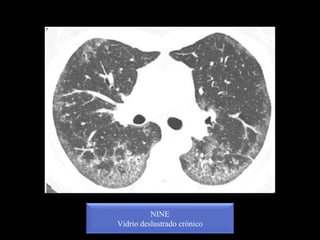

NINE

Vidrio deslustrado crónico